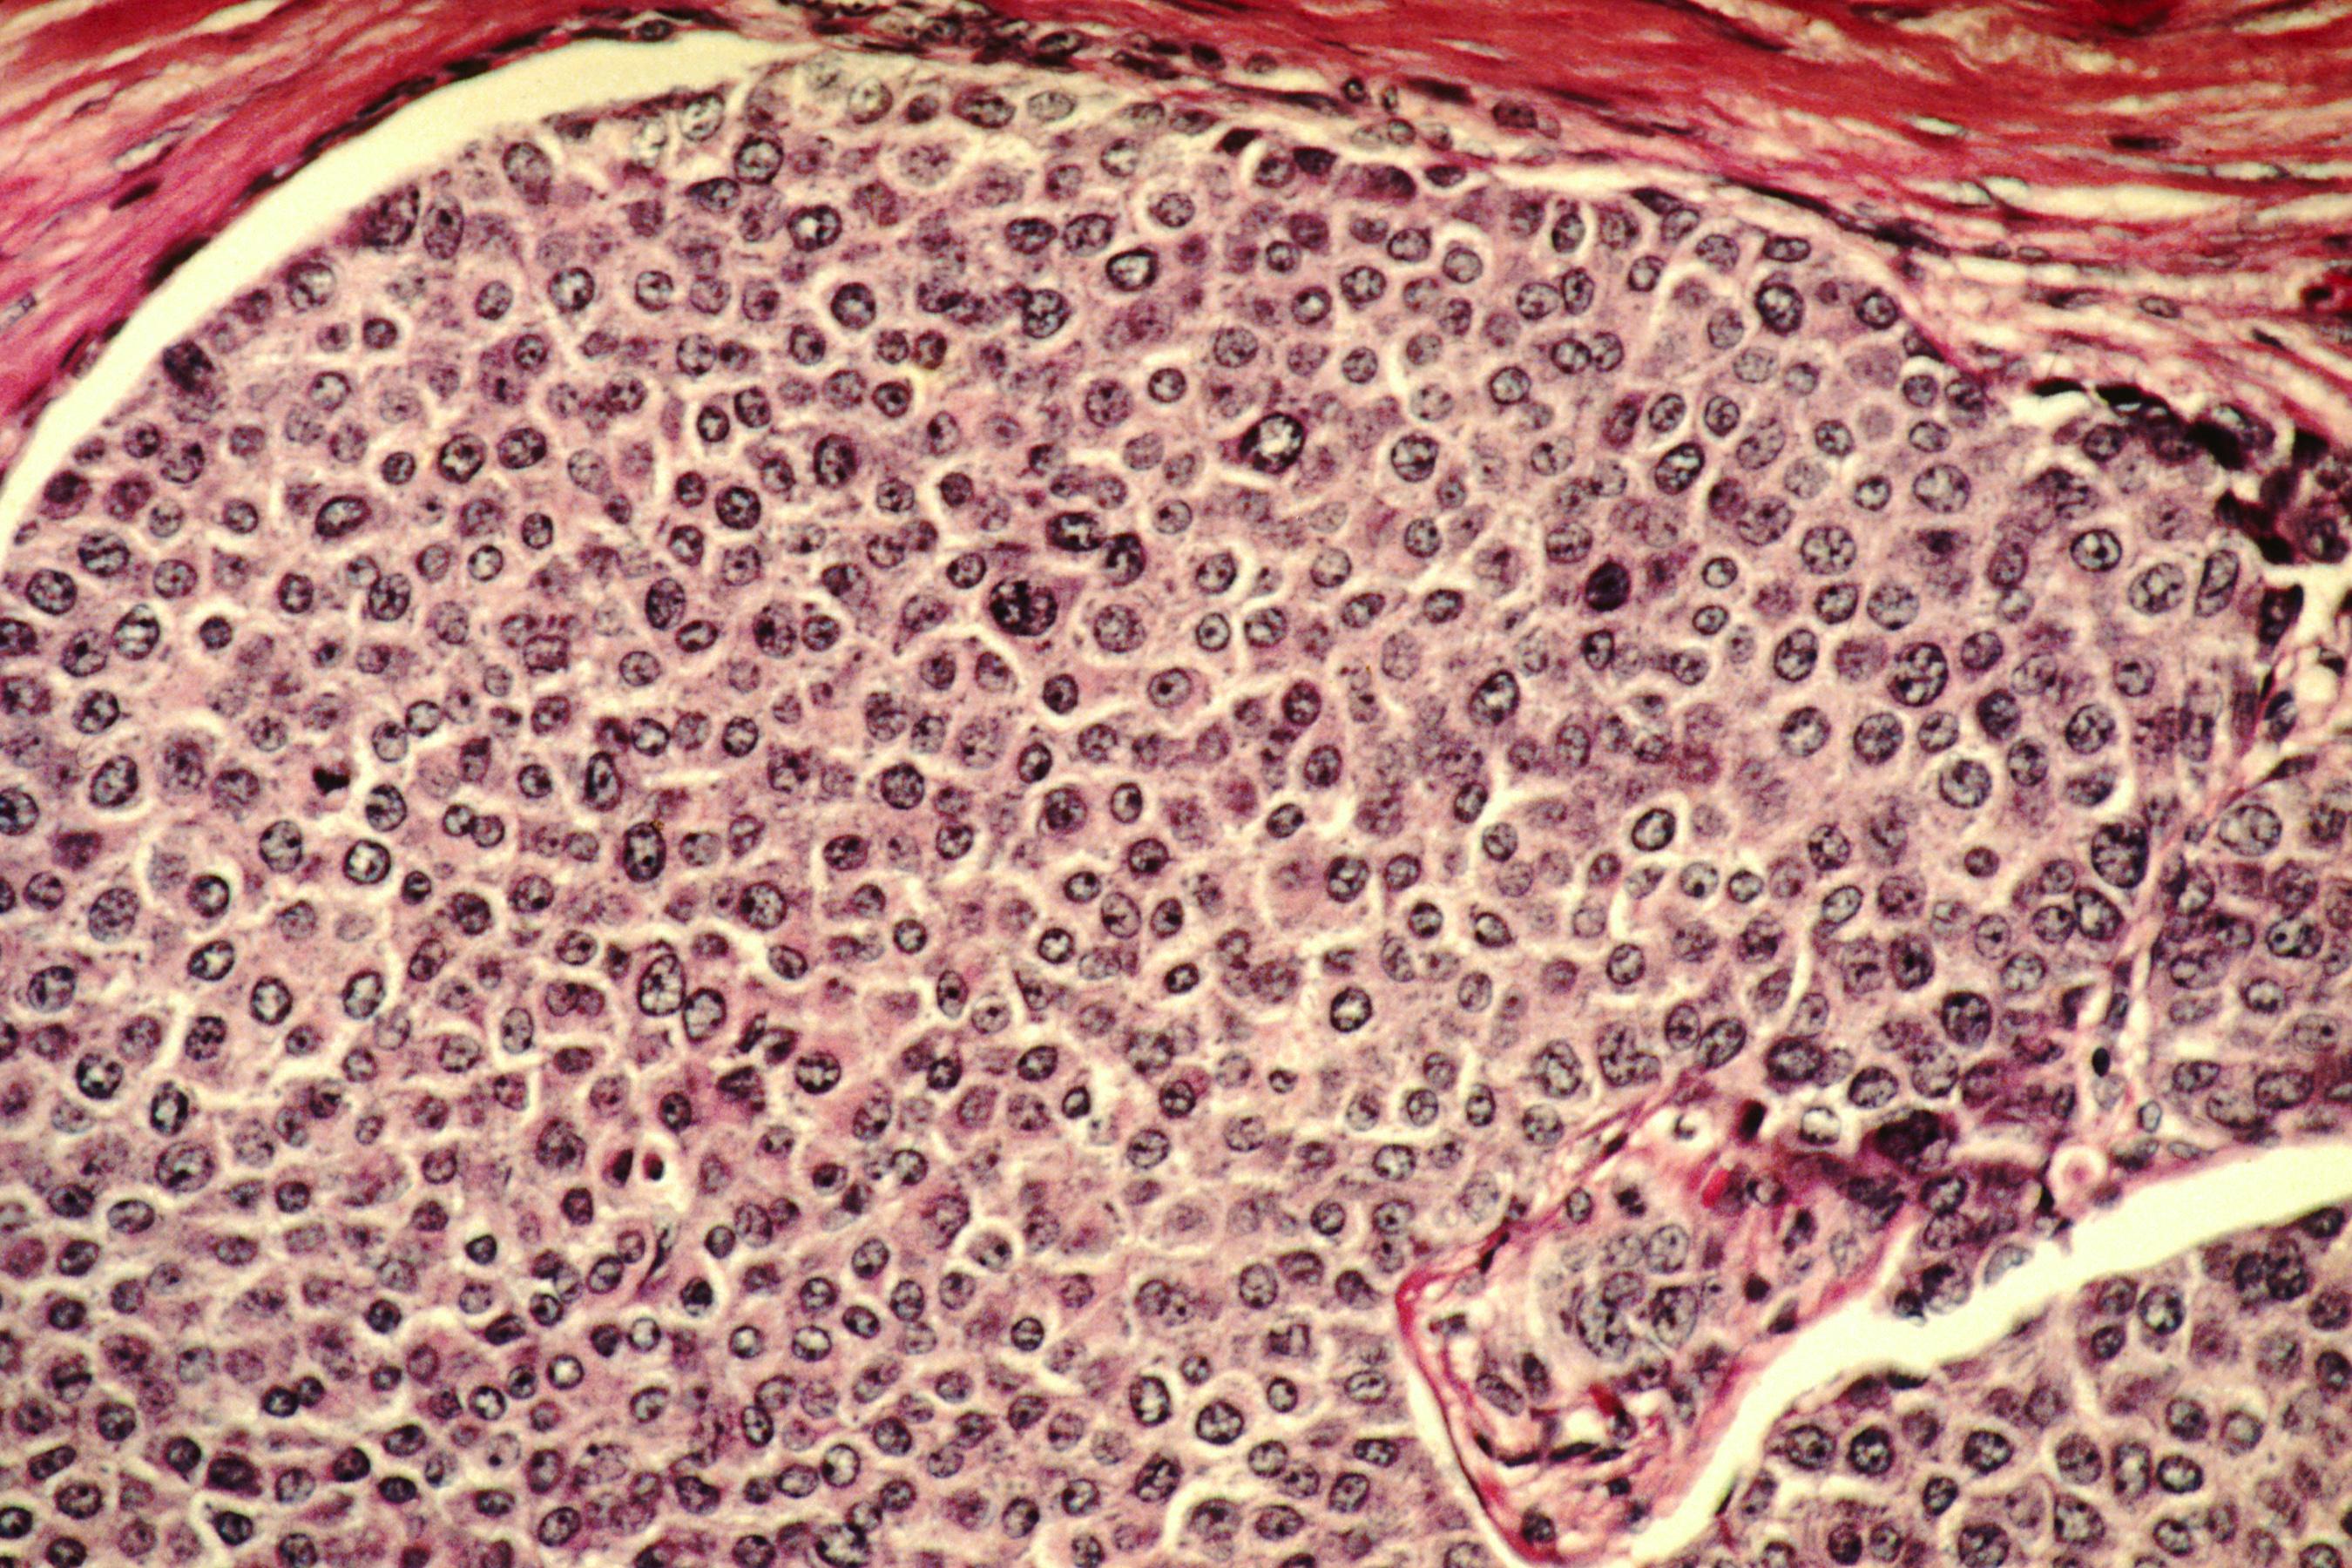

Раковая шишка – это заболевание, которое поражает кожу и слизистые оболочки. Она может возникнуть в различных частях тела и иметь различные внешние проявления. В данной статье мы представляем вам многочисленные фотографии раковых шишек, чтобы вы могли узнать, как они выглядят.

Одной из наиболее распространенных локализаций раковых шишек является лицо. На фото вы можете увидеть различные типы раковых шишек, такие как базалиома, плоскоклеточный рак и меланома. Обратите внимание на характерные признаки каждого типа раковой шишки, такие как изменение цвета, формы и размера.

Раковые шишки могут возникать не только на лице, но и на других частях тела. На фотографиях вы можете увидеть примеры раковых шишек на шее, руках, ногах и туловище. Обратите внимание на различные формы и размеры раковых шишек, а также на их внешний вид.